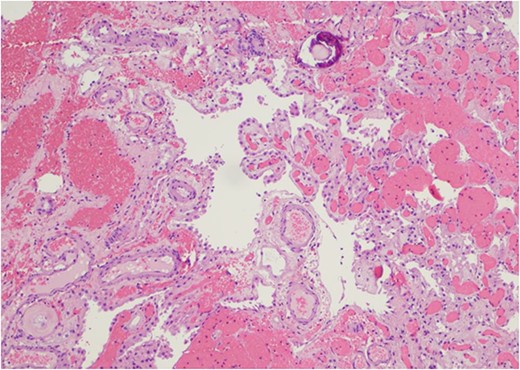

Only one small piece of the cystic lesion was obtained and entirely submitted for touch preparation and frozen section (Fig. 2), which demonstrated a hypercellular lesion composed of uniform ovoid cells with salt-and-pepper chromatin, lacking pleomorphism, grooves, nucleoli, increased mitotic activity, and had no papillary architecture. The intraventricular lesion was submitted separately and had the morphology of a benign papilloma (Fig. 3), staining with cytokeratin AE1/AE3, with no staining with GFAP. Because of the histological discrepancy of the first and second specimens, and the limited amount of tissue from the cystic lesion, the paraffin embedded tissue of the cystic lesion was submitted for methylation profiling by NIH. The methylation profiling had a maximum score of 1 for both class and subclass for EVN, WHO grade 2 (Fig. 4).

The intraventricular tumor consisted cuboidal epithelium overlying vascularized papillae. The nuclei are uniform without atypia. A psammomatous calcification is present in the upper portion of the field (Hematoxylin and eosin, 100×).